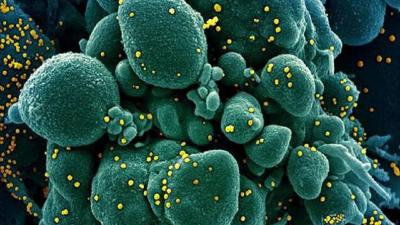

कोरोना व्हायरसने संपूर्ण जगभरात वर्षभरापासून हाहाकार पसरवला आहे. कोरोना व्हायरसच्या संक्रमणातून बाहेर आलेल्या लोकांसाठी एक नकारात्मक माहिती समोर येत आहे.

अमेरिकेतील टेक्सासमधील टेक युनिव्हर्सिटी ऑफ हेल्थ सेंटरच्या साहाय्याक प्राध्यापक डॉ. ब्रिटनी केंडेल यांनी केलेल्या दाव्यानुसार कोरोनावर मात केलेल्या लोकांना या आजाराच्या दीर्घकालीन परिणामांचा सामना करावा लागेल. तसंच त्यांची फुफ्फुसं स्मोकिंग करत असलेल्या लोकांच्या तुलनेत जास्त संवेदनशील होऊ शकतात.

कोरोनाच्या संक्रमणानंतर फुफ्फुसांवर तीव्र परिणाम होण्याची शक्यता असते. हा आजार उद्भवल्यास रुग्णाला श्वास घ्यायला त्रास होतो. हळूहळू रुग्णांच्या शरीरात ऑक्सिजनची कमतरता भासायला सुरूवात होते. अनेकदा या लक्षणांची कारणं कळून येत नाहीत.या कंडीशनला डॉक्टरर्स इडियोपॅथिक पल्मोनरी फायब्रोसिस असं म्हणतात.(ImageCredit- Aajtak)